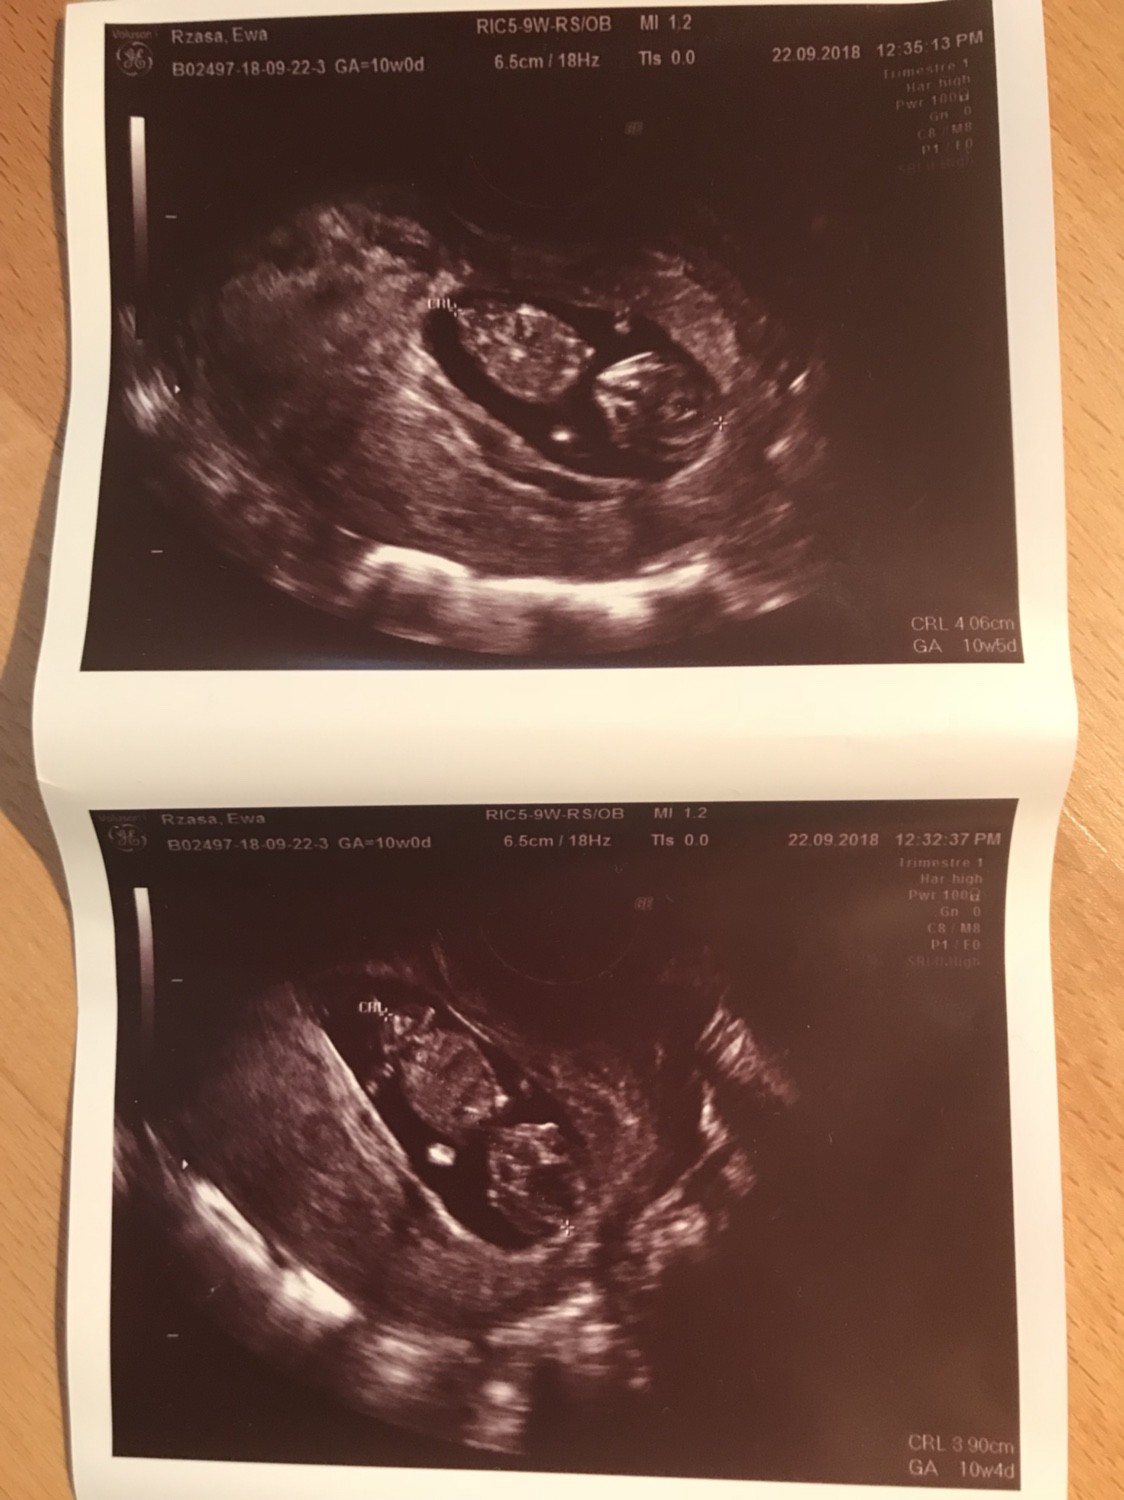

Ja tez mialam dzis wizyte, wracalam z londynu 4 godziny w korku, myslalam, ze uswierkne w samochodzie! Z maluszkiem jest wszystko w porzadku[emoji173]️, 4cm 10+4/5wiec praktycznie co do dnia zgadza sie z transferem, krwiaczek sie wchlonal i jest ok. Maluszek machal raczkami i jakies koziolki fikal, az trudno uwierzyc, ze tam w srodku taka impra sie odbywa ;) wiec jak narazie kamien z serca i czekam na prenatalne 3 pazdziernika. A tu fota kosmity i wracam dalej nadrabiac forum. :)Zobacz załącznik 900663

[emoji7][emoji7][emoji7] piekny maly czlowieczek